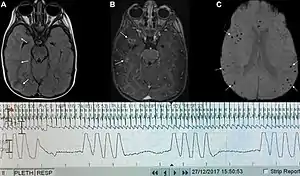

| Graph showing Biot's respiration and other pathological breathing patterns. | |